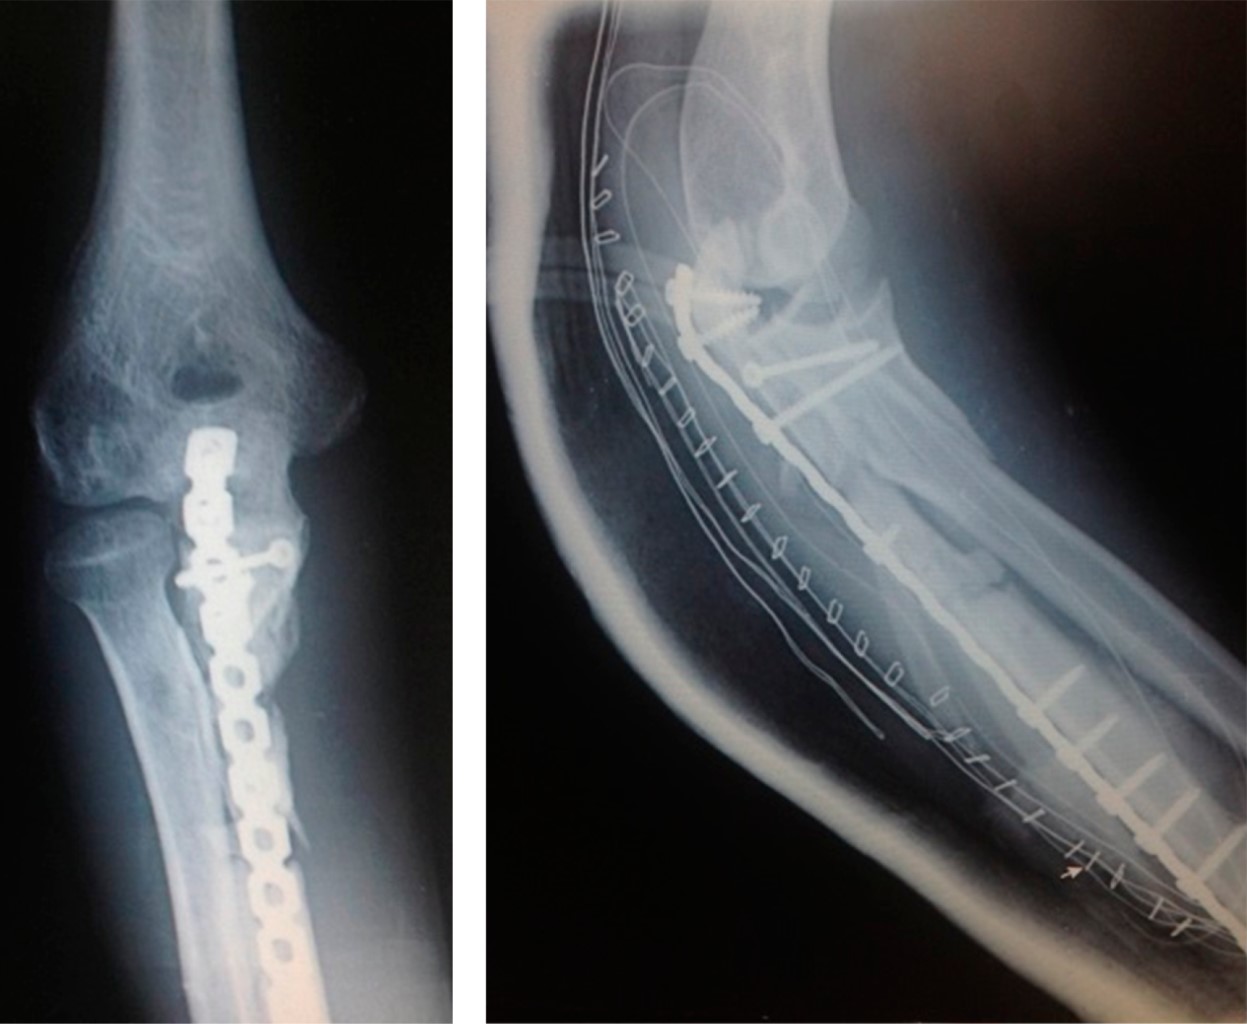

Radiológicamente (Figura 5), había consolidación con malalineación del cúbito proximal y sinostosis radiocubital proximal. Clínicamente, el paciente tenía gran limitación de la pronosupinación, flexión de codo de 100° y un déficit de 50° de la extensión. El paciente evolucionó favorablemente, sin presentar infección y con reepitelización completa del antebrazo. La Figura 6 muestra el resultado cutáneo a los seis años y medio.